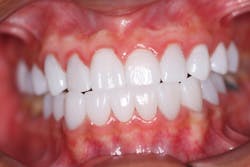

No. 3: Mandibular arch

- Followed same protocol

- Final lithium disilicate restorations (IPS e.max; figure 3)